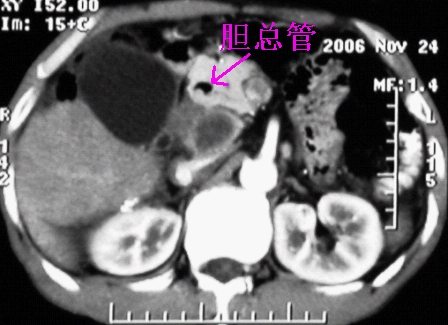

增强ct所见

门脉主干及肠系膜上静脉近端明显增粗,尤其前者呈等低混杂密度,增强后周围见轻度环形强化。明显占位效应。肝内外胆管见大量气体影。胆囊明显增大。

胆囊增大,边缘模糊,胆囊炎可考虑。胆总管及部分肝内胆管充气,考虑胆管炎。

1、胰头部占位:胰管轻度扩张(可疑双管征),主要考虑恶性肿瘤,胰头癌?十二指肠间质瘤?后腹膜肿瘤?

3、胆囊积液、肝胆管积气、胆道扩张伴有胆道感染;